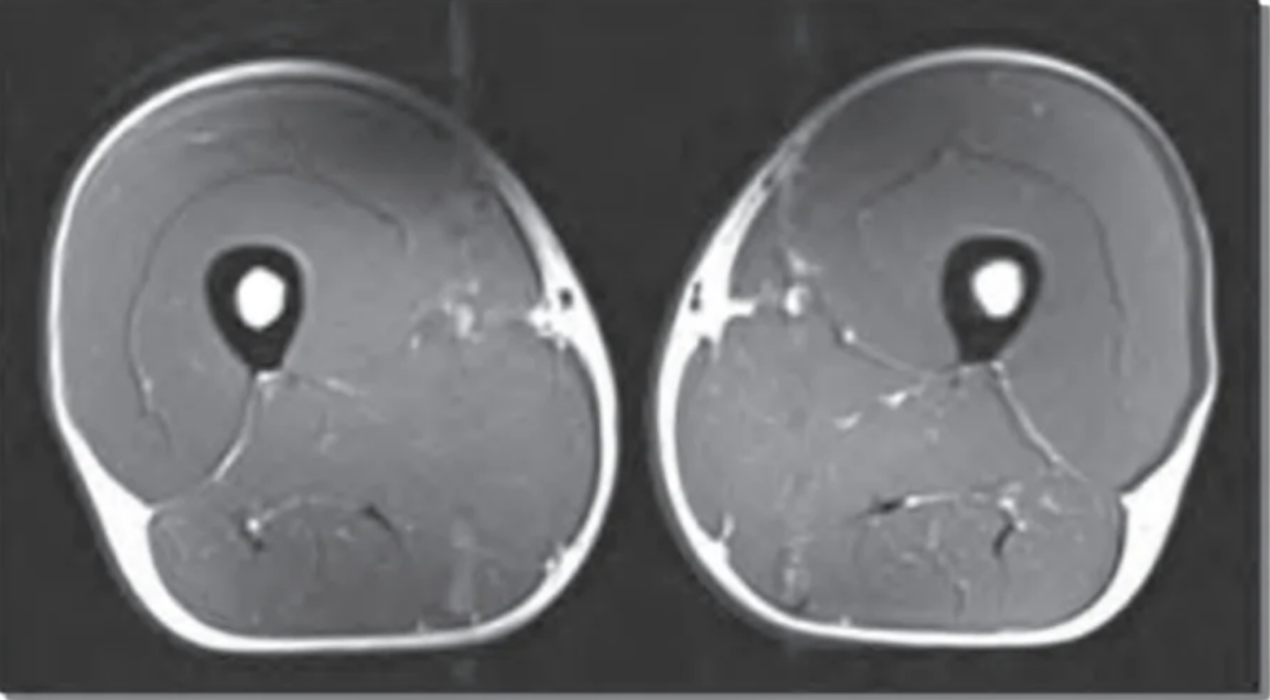

Hier ist ein MRT-Bild der Oberschenkel einer meiner 50 Jährigen, gesunden Patienten:

Und hier ist ein Bild von den Oberschenkeln eines anderen 50-jährigen Patienten mit Sarkopenie:

Was die Person aus dem ersten Bild anders gemacht hat und wieso sie selbst mit 50 Jahren noch fit wie mit 20 ist…

…während der andere Patient schon nach zwei Stockwerken außer Puste ist, erzähle ich dir gleich!